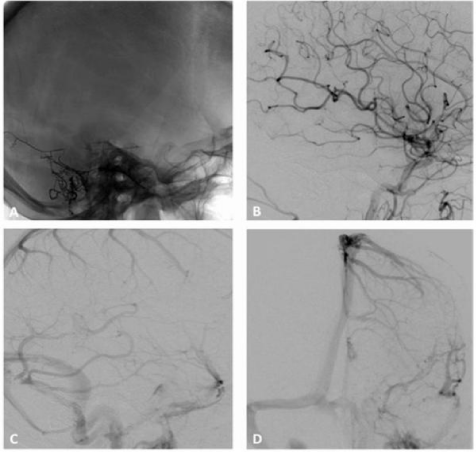

Figure 4 A (anteroposterior) and B (lateral), radiography showing the cast of Onyx obliterating the parietal branches of the middle meningeal artery with arterioarterial reflux into homolateral feeders, the cast extending to the arteriovenous junction and the proximal venous outflow. C Anteroposterior and D lateral projections DSA of the common carotid artery demonstrating a complete obliteration of the fistula.

Figure 7 A, B, right and C left external carotid artery injections DSA confirms a Borden grade III IDAVF with venous ectasias (asterisk), which corresponds to Cognard grade IV, with bilateral arterial supply from the middle meningeal and superficial temporal arteries and direct CVD through dilated pial veins tributary of the superior sagittal sinus. D, Lateral projection DSA does not show ICA supply to the fistula.